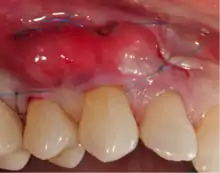

Technique

Gums sutured during a graft

A small amount of blood (10 millilitres (0.35 imp fl oz; 0.34 US fl oz) per tube) is harvested and spun in a centrifuge for eight minutes at 1300 rpm. A fibrin clot packed with blood-derived growth factors, extra cellular matrix and hematopoietic stem cells is fabricated and implanted into the gums above the area of gum recession. Advanced platelet-rich fibrin will promote the patient's own gums to fabricate more gum thus eliminating the need to harvest gums from the roof of the mouth or the use of allografting tissue.